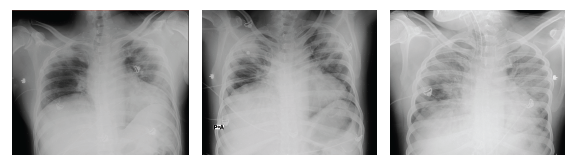

On November 28, 2020, the patient presented anxiety and increased dyspnea. Laboratory tests showed leukocytosis with neutrophilia and increased bilateral infiltrates in both lung fields in the chest X-ray, evolved with progressive deterioration of general condition with severe hypoxemia in the context of Acute Respiratory Distress Syndrome (ARDS) that required orotracheal intubation, connection to mechanical ventilation with requirements of high Fio2, and management of airway pressures. Progression to multi-systemic organ failure with need for vasopressor support. During the 10 days in which the patient remained intubated, he received psychological support, and a family member (who received psychological support throughout the patient's stay in the unit) was allowed daily admission. The hospital authorized psychological and family support during the patient's stay in the COVID intensive care unit. On leaving the ICU, the patient mentioned that, under sedation, he felt the support of his therapist: in the reverie produced by the effect of the sedatives, he visualized her sitting next to him, accompanying him, and sending him rays of light, and he commented that he felt very calm at that moment. He would ask her: "How long will I be here? How are we doing?" And he received an answer from the therapist, not in words, but mentally: "calm down, it won't be long, everything will be all right". He affirms that he saw her smiling and assured of what she was saying, and he felt very calm. He also commented that he heard, on several occasions, the doctors and nurses talking to each other, and he was very anxious when he knew from what he heard that things were not going well. The patient and his family received daily psychological therapy support during his stay in the hospital.